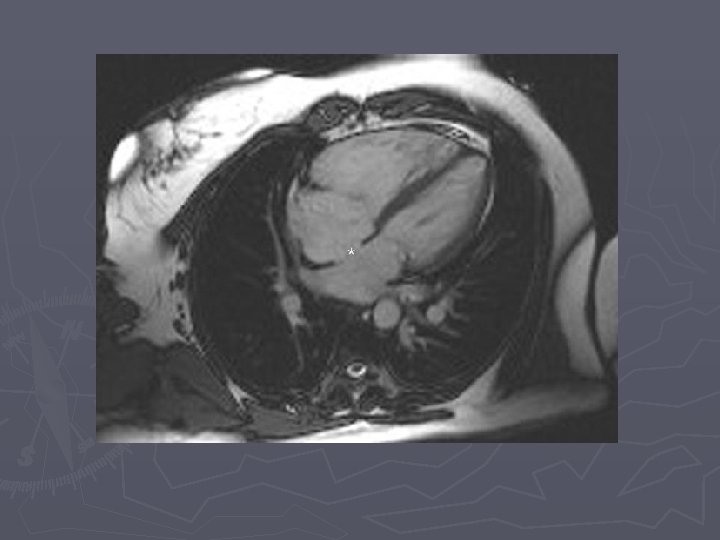

Imaging ASD ► Primary diagnosis made by echocardiography in infants and children ► MRI is emerging as accurate alternative for depiction of function, flow, and anatomy in older patients

Findings ► XR – small to moderate defects have normal radiographs ► XR - large defects have cardiomegaly with the main PA normal or enlarged, with shunt vascularity, later on PA and RV enlarge ► CTA – defect in atrial septum, enlargement of RA, RV and PA ► MR – can quantify shunt volume on volumetric cine MR or velocity encoded cine MR